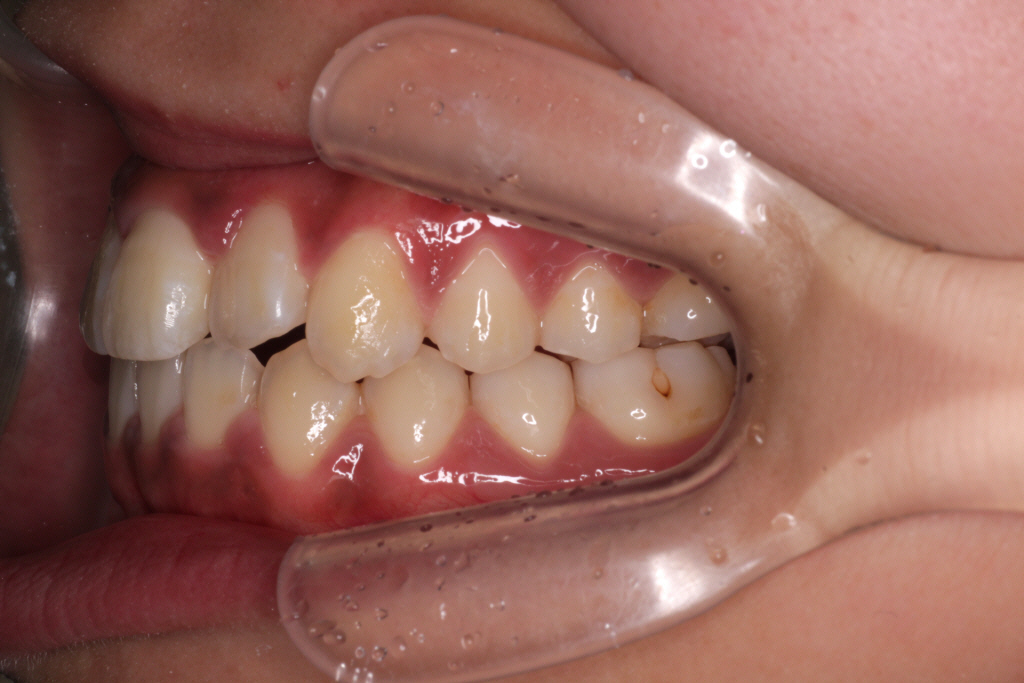

初診時のお口の中の状態です。

上の前から2番目の歯が下の歯列より内側にあり叢生です。

側方の上下の咬合関係が理想の上1本に対して下2本の理想的な噛み合わせではない。

歯列の幅がせまい。

診断:上顎前突・前歯部叢生